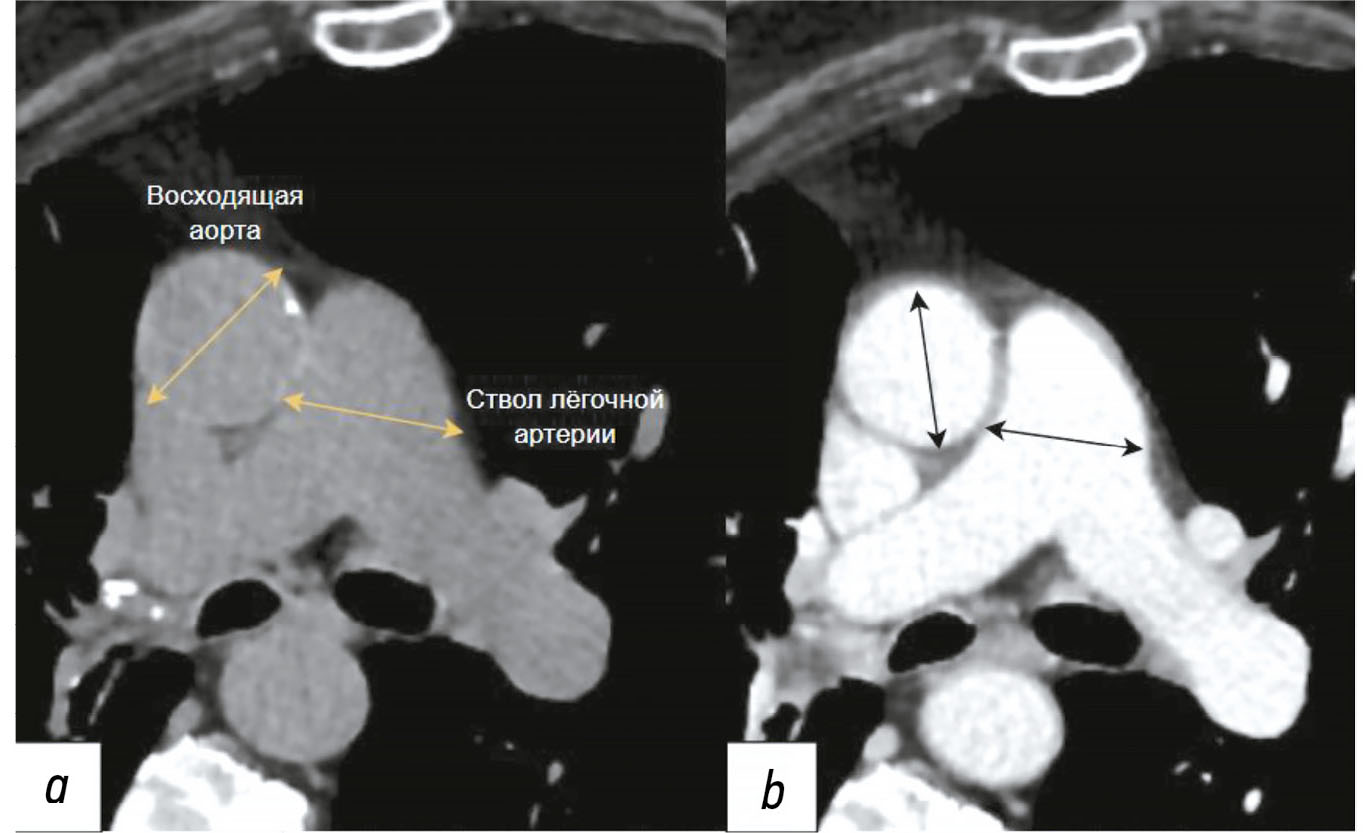

Существует статистически значимая связь между соотношением диаметра лёгочного ствола к диаметру восходящей аорты и повышенным риском смерти, независимо от наличия ишемической болезни сердца. Предложено выполнять измерение соотношения между максимальными диаметрами ствола лёгочной артерии и восходящим отделом грудной аорты. Нормальное значение индекса составляет ≤1, в свою очередь, его величина >1 указывает на расширение ствола лёгочной артерии. Согласно рекомендациям ESC/ERS от 2022 года и клиническим рекомендациям Министерства здравоохранения Российской Федерации от 2024 года, пороговое значение индекса пересмотрено с 1 на 0,9 [9, 86]. Данное соотношение может способствовать клинической оценке и прогнозированию течения лёгочной гипертензии [90–94]. Пример измерения диаметра аорты и лёгочной артерии по данным КТ показан на рис 1.

Рис. 1. Пример измерения соотношений ствола лёгочной артерии и восходящей аорты. На аксиальном срезе изображений компьютерной томографии на уровне бифуркации лёгочной артерии проведено измерение диаметров лёгочной артерии и восходящей аорты. Использовали компьютерный штангенциркуль, который фиксировал наибольший диаметр сосудов по вертикали от длинной оси главной лёгочной артерии: a — с применением контрастного усиления; b — без его применения.

Лёгочный ствол обычно измеряют в месте его раздвоения перпендикулярно длинной оси на аксиальном срезе, на этом же уровне определяют диаметр всходящей аорты при расчёте их соотношения [90]. Лучевые биомаркёры, такие как диаметр лёгочного ствола и вторичные признаки сердечной недостаточности, в частности расширение нижней полой вены, плевральный выпот и уплотнение лёгочной ткани по типу «матового стекла», также являются важными для определения лёгочной гипертензии. Отношение диаметров лёгочного ствола к восходящей аорте, превышающее 1, обладает специфичностью 92% в отношении выявления повышенного среднего артериального давления более 20 мм рт. ст. [88].